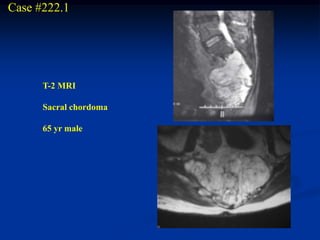

Case #222.1

T-2 MRI

Sacral chordoma

65 yr male

Rebar and cement reconstruction